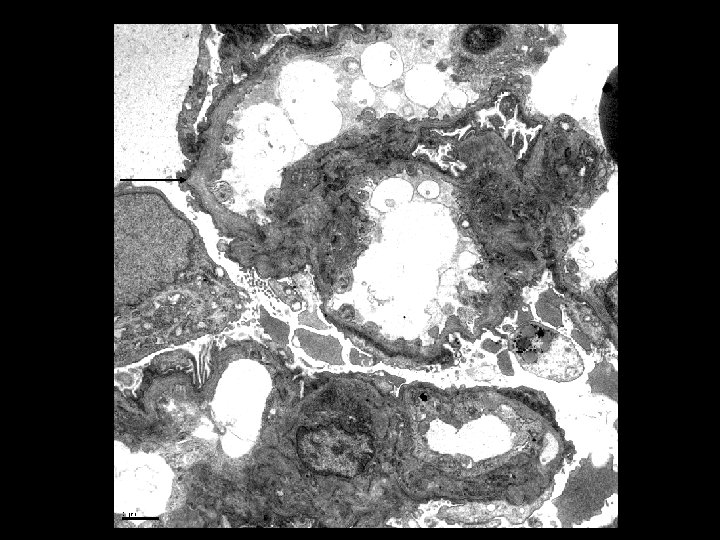

Electron Microscopy • Lamellation, thickening and thinning of GBMs

Alport’s Syndrome • Recurrent hematuria • Nerve deafness • Usually presents in early 20’s • Classic renal biopsy features by EM – Thickened and Thinned GBM – Lamination and Rarefaction – Grains